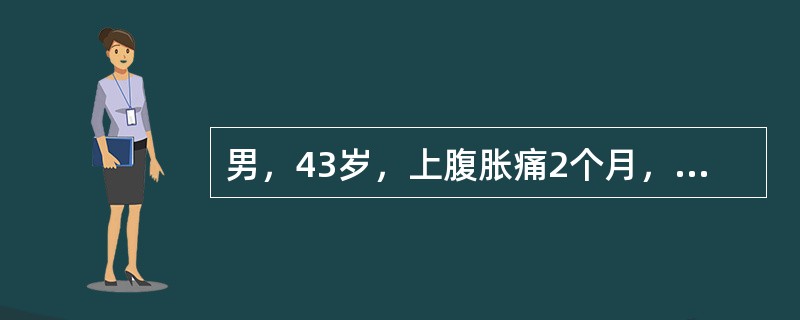

男,43岁,上腹胀痛2个月,频繁呕吐,呕吐物为黄绿色,影像所见如图,可能的诊断为()

男,43岁,上腹胀痛2个月,频繁呕吐,呕吐物为黄绿色,影像所见如图,可能的诊断为

[单选题]男,43岁,上腹胀痛2个月,频繁呕吐,呕吐物为黄绿色,影像所见如图,可能的诊断为()A .十二指肠溃疡B .十二指肠结核C .十二指肠中分化腺癌D .十二指肠克罗恩病E .十二指肠淋巴瘤